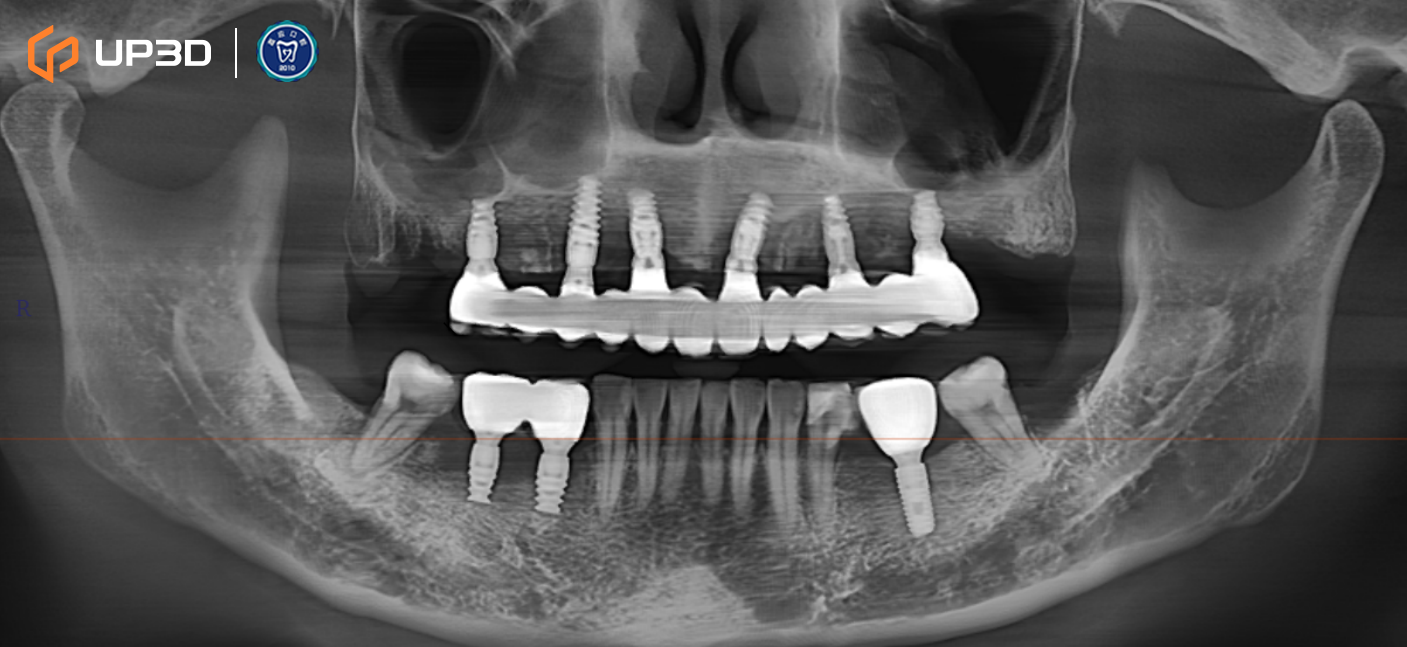

2.3 Radiographic Assessment

A panoramic radiograph and cone-beam computed tomography (CBCT) revealed multiple missing teeth and uneven alveolar ridge resorption, with moderate-to-limited bone volume in selected areas. Based on measurement and analysis, implant placement was planned at sites including 16, 14, 12, 21, 24, 26, 36, 45, and 46 (FDI tooth numbering).

Intraoral scan data were merged with CBCT to complete a 3D implant plan:

-

Six implants planned in the maxilla and three implants in the mandible

Surgical guide (guided surgery) pathways were planned digitally

Digital tooth setup and guide fabrication supported accurate positioning and a minimally invasive approach

Guided surgery helped improve consistency in implant angulation and depth control, supporting a stable foundation for immediate loading.

8.2 Three-Month Follow-Up

Panoramic imaging showed stable implant and prosthesis positioning

Occlusion remained stable, with no evident peri-implant bone changes on follow-up imaging